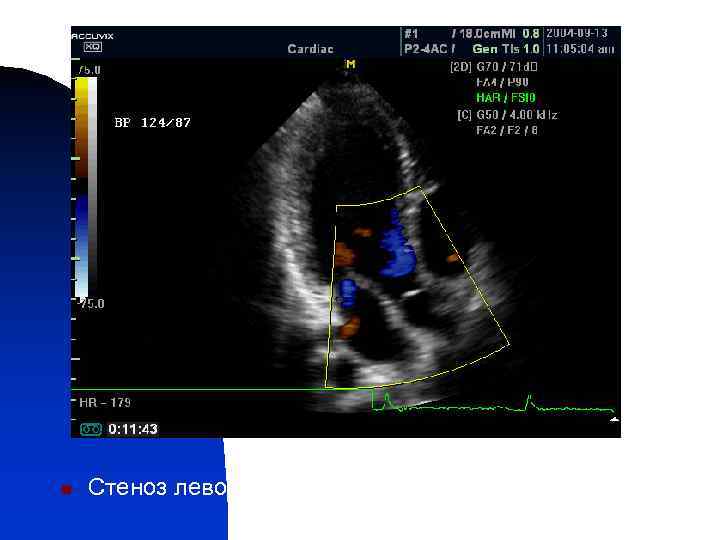

n Стеноз левого атрио-вентрикулярного отверстия

n Mitral valve, regurgitation, color doppler (video). Ultrasound image.